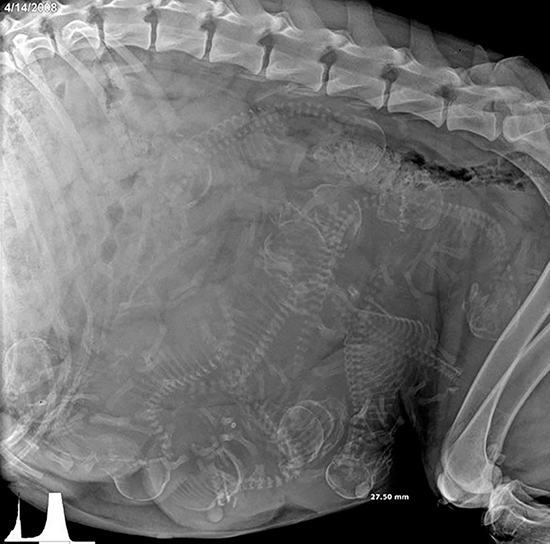

عکس اشعه ایکس از سگ باردار